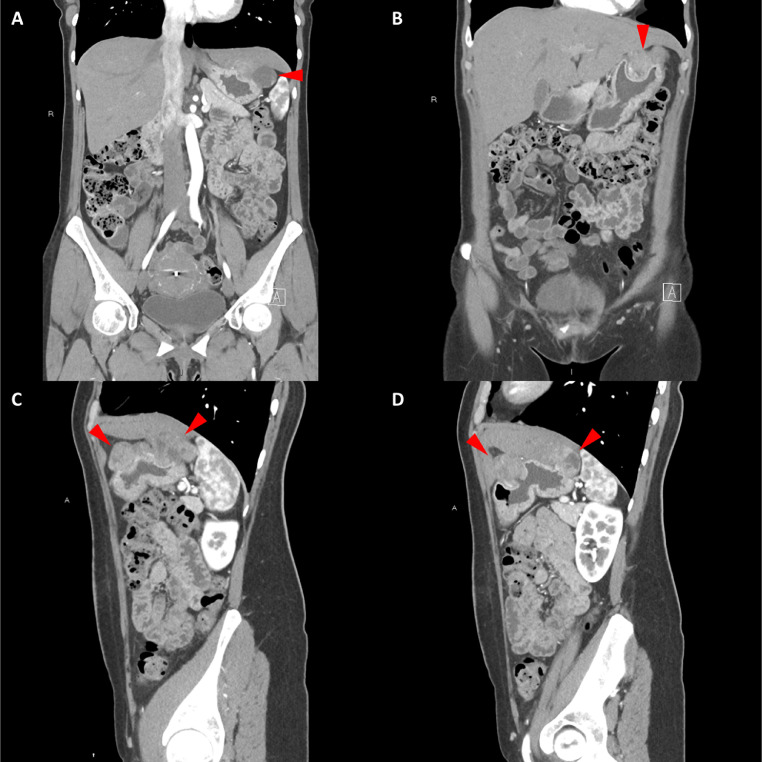

頸部增強(qiáng) CT 顯示 2 個(gè)強(qiáng)烈強(qiáng)化的腫塊。 一個(gè)位于頸部右側(cè),位于右側(cè)頸內(nèi)動(dòng)脈后方的頸動(dòng)脈間隙中,位于莖突內(nèi)側(cè),大小為 24 × 24 × 30 mm,頸靜脈橫向移位(圖 1A)。 第二個(gè)位于左側(cè)頸動(dòng)脈間隙,在分叉處正上方展開(kāi)頸外動(dòng)脈和頸內(nèi)動(dòng)脈,尺寸為 15 × 18 × 22 mm(圖 1B)。 影像學(xué)檢查結(jié)果與右側(cè)迷走神經(jīng)和左側(cè)頸動(dòng)脈體副神經(jīng)節(jié)瘤一致,與之前的活檢結(jié)果一致。

Fig. 1

圖1:右側(cè)迷走神經(jīng)和左側(cè)頸動(dòng)脈體副神經(jīng)節(jié)瘤。 (A) 軸位增強(qiáng) CT 顯示右側(cè)頸動(dòng)脈間隙、右側(cè)頸內(nèi)動(dòng)脈后方(白色箭頭)和莖突內(nèi)側(cè)有強(qiáng)烈強(qiáng)化的腫塊(紅色箭頭)。 (B) 軸位對(duì)比增強(qiáng) CT 顯示左頸動(dòng)脈間隙有強(qiáng)烈強(qiáng)化的腫塊(紅色箭頭),向后張開(kāi)頸內(nèi)動(dòng)脈(紅色箭頭),向前張開(kāi)頸外動(dòng)脈(紅色箭頭)。 (C) 冠狀對(duì)比增強(qiáng) CT 顯示兩個(gè)增強(qiáng)腫塊(紅色箭頭)。